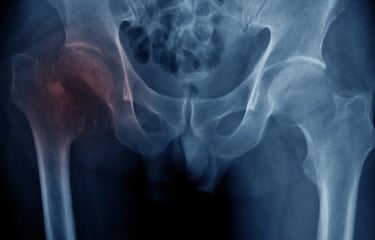

Avulsion fracture

Avulsion fractures happen when a bone fragment separates from the rest of the bone. In children, they are most common in sports like soccer, football, gymnastics, and other sports that involve sudden changes in direction, leaping, and kicking.